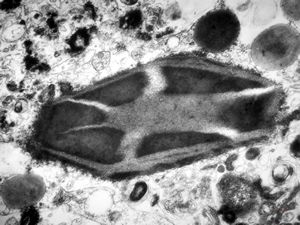

M,15y. | eosinophilic granuloma - Charcot- Leyden crystals

M,15y. | eosinophilic granuloma - Charcot-Leyden crystal

F,1y. | eosinophilic granuloma - Charcot- Leyden crystal